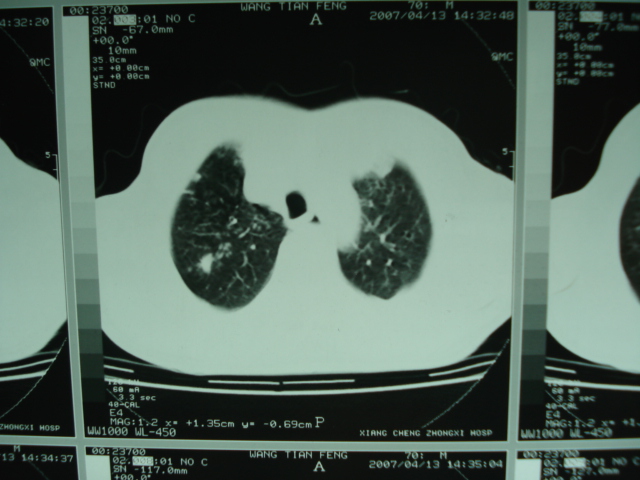

以下是引用狙击手在2007-4-18 20:17:00的发言:[br]原:2007/1/22号ct片:右肺上叶可见片状、云雾状高密度影,右肺上叶后段可见三角形高密度影,尖端指向肺门,右肺上叶后段支气管壁不规则增厚,管腔不规则增厚,纵隔未见肿大淋巴结.[br] 今ct:右肺上叶片状影增大,右肺上叶后段不张及右肺上叶后段支气管壁不规则增厚未见变化,右肺下叶背段支气管壁不规则增厚.[br] 如果考虑肺结核,但从临床证据看竟然没有一项支持肺结核,不知患者是否已经过正规抗结核治疗。没有的话,3个月了前后片看起来变化不大,似乎有不太符合肿瘤征象,不知患者是否抗炎治疗过,下叶支气管增粗还是要高度警惕,同意楼主意见,将常规病理,生化检查再做一遍。[br]

以下是引用狙击手在2007-4-18 20:17:00的发言:[br]原:2007/1/22号ct片:右肺上叶可见片状、云雾状高密度影,右肺上叶后段可见三角形高密度影,尖端指向肺门,右肺上叶后段支气管壁不规则增厚,管腔不规则增厚,纵隔未见肿大淋巴结.[br] 今ct:右肺上叶片状影增大,右肺上叶后段不张及右肺上叶后段支气管壁不规则增厚未见变化,右肺下叶背段支气管壁不规则增厚.[br] 如果考虑肺结核,但从临床证据看竟然没有一项支持肺结核,不知患者是否已经过正规抗结核治疗。没有的话,3个月了前后片看起来变化不大,似乎有不太符合肿瘤征象,不知患者是否抗炎治疗过,下叶支气管增粗还是要高度警惕,同意楼主意见,将常规病理,生化检查在做一遍。[br]